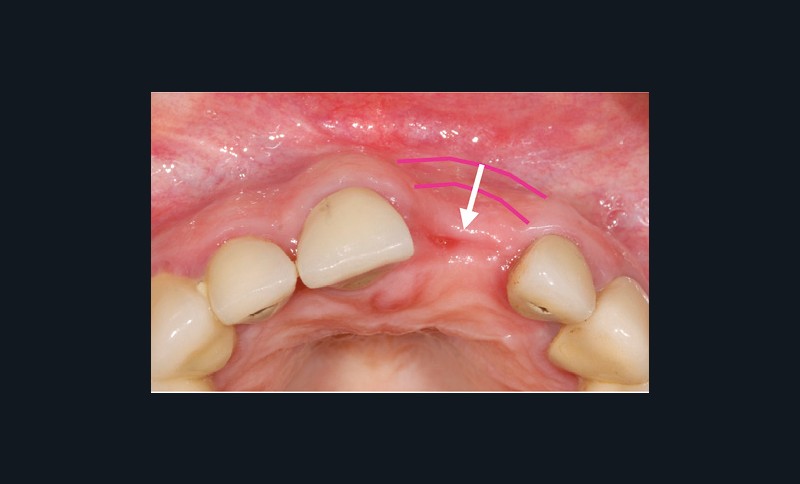

Lorsque la crête est déjà édentée, la résorption osseuse a déjà eu lieu et, en conséquence, la morphologie des tissus mous est altérée (fig. 1). Il faut alors utiliser des techniques d’augmentation osseuse et/ou muqueuse afin d’obtenir une architecture des tissus mous la plus naturelle possible.

L’architecture des tissus doit se visualiser en trois dimensions et comprend deux zones : la zone des papilles et celle de la gencive marginale, avec leurs composantes verticales, horizontales et la profondeur. L’autre aspect de cette architecture est lié aux types de tissus mous (muqueuse alvéolaire…